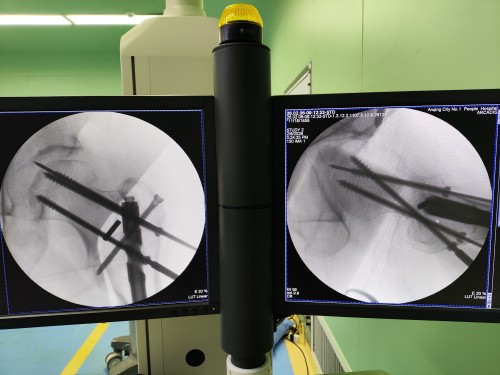

术中机器人导航图

术前通过三维影像重建精准规划螺钉植入路径,巧妙避开髓内钉;术中机器人导航系统实时引导手术器械,实现毫米级精度的骨折复位与螺钉植入。手术全程无需取出原有髓内钉,亦无需大切口开放,创伤极小、几乎无出血。术后患者生命体征平稳,髋部疼痛即刻缓解,第二天即可在医护指导下进行功能锻炼,第三天便顺利出院。